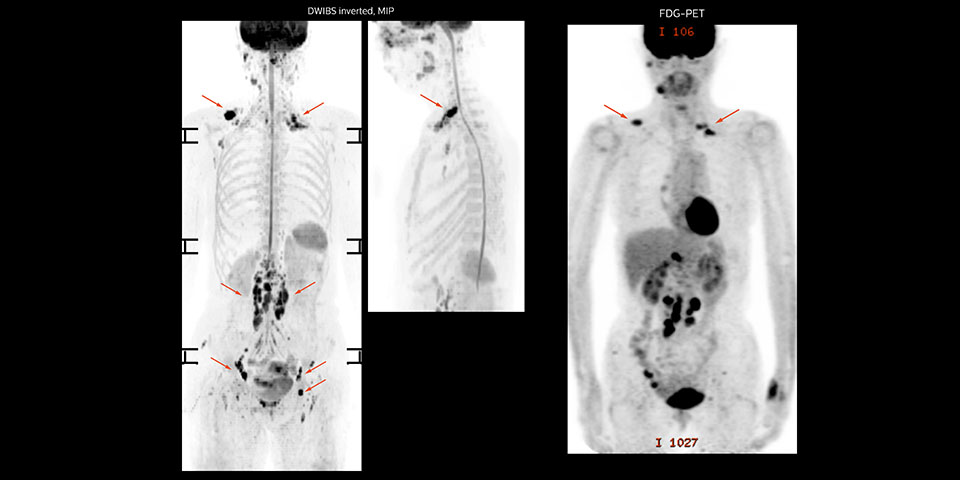

MR-Untersuchung einer 61-jährigen Patientin mit einem malignen Lymphom mit diffusionsgewichteter Ganzkörper-MRT sowie PET. Auf den gezeigten Bildern ist die Auflösung mit der diffusionsgewichteten MRT besser als mit der PET, die eine Darstellung der kleinen Beckenläsionen ermöglicht; im Halsbereich ist praktisch keine Verzerrung zu erkennen.